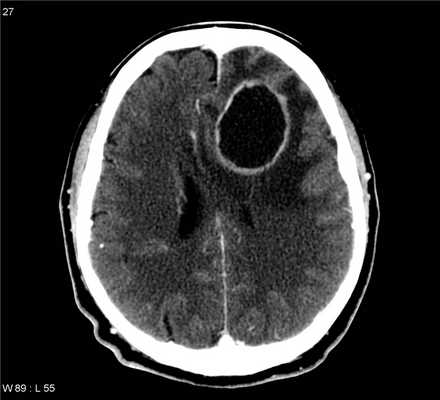

КТ

У пациентов с подозрением на абсцесс должны получены пре- и постконтрастные изображения при невозможности выполнения МРТ.

Типичные признаки:

• изо- или гиперденсивное кольцо ткани равномерной толщины

• центральное низкое затухание (жидкость/гной)

• окружающая область низкой плотности (вазогенный отек)

• вентрикулит

• обструктивная гидроцефалия возможна при внутрижелудочковом прорыве

Точность диагностирования с помощью КТ головного мозга зависит от стадии формирования абсцесса. На ранних стадиях заболевания диагностика затруднена. На этапе раннего энцефалита (1-3 сутки) КТ определяет зону сниженной плотности неправильной формы. Введенное контрастное вещество накапливается неравномерно, преимущественно периферических отделах очага, реже в центре.

На более поздних этапах энцефалита контуры очага приобретают ровные округлые очертания. Контрастное вещество распределяется равномерно, по всей периферии очага; плотность центральной зоны очага при этом не меняется. Однако на повторной КТ (через 30-40 минут) определяется диффузия контраста в центр капсулы, а также наличие его и в периферической зоне, что не характерно для злокачественных новообразований.

Инкапсулированный абсцесс мозга на КТ имеет вид округлого объемного образования с четкими ровными контурами повышенной плотности (фиброзная капсула). В центре капсулы зона пониженной плотности (гной), по периферии видна зона отека. Введенное контрастное вещество накапливается в виде кольца (по контуру фиброзной капсулы) с небольшой прилежащей зоной глиоза.

На повторной КТ (через 30-40 минут) контрастное вещество не определяется. При исследовании результатов компьютерной томографии следует учесть, что противовоспалительные препараты (глюкокортикостероиды, салицилаты) в значительной степени влияют на скопление контраста в энцефалитическом очаге.